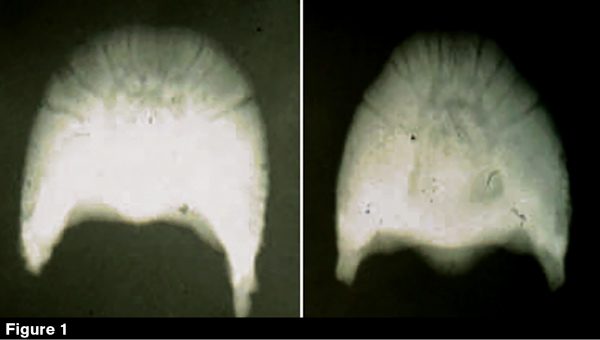

Butler illustrated managing club feet using a Morgan pleasure show horse (Figures 3a, 3b, 3c, 3d) that requires frequent maintenance.

The horse had a steep pastern, which required Butler to pull the shoe back to remove the dish from the front of the foot. This exposed the scarred horn from the mild laminitis that’s occurring in the foot. Because this was a show horse, the toe was blackened and the hole was filled in. In this situation, a veterinarian also could have performed a subcarpal check ligament desmotomy to help the muscles to stretch.